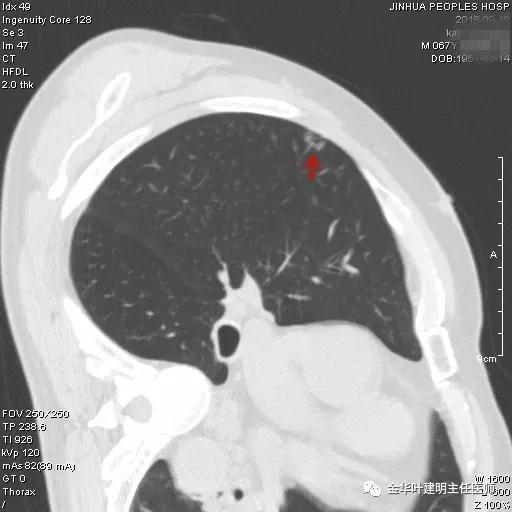

上图示左下支扩及感染

靶扫描以后还发现上叶另外地方还有一磨玻璃结节,约1厘米左右,密度较淡,但瘤肺边界清楚,也是较为典型的腺癌影像:

如此,右上肺是多发磨玻璃结节,考虑多原发癌。按病灶大小及所处部位,需要行右肺上叶切除,并淋巴结采样或清扫。鉴于其存在肺部炎症情况,建议其先抗炎治疗7-10天,待咳嗽、咳痰症状不明显,血象及C-反应蛋白等均正常后再考虑行胸腔镜下微创手术,因为合并肺部炎症情况下手术,术后呼吸道并发症发生率增高,也容易出现肺不张、支气管胸膜瘘或低氧血症等相关风险。